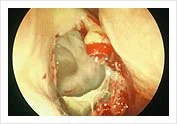

Endoscophic Drainage of Ethmoidal Mucocele during and end of operation

Intra-operative endoscopic drainage of the ethmoidal mucocele.

Cavity left alone to heal with good drainage and ventilation.